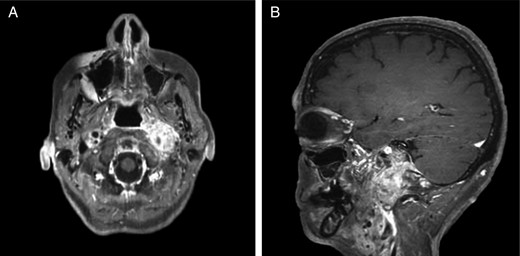

Repeat magnetic resonance imaging (Figs. 3 and 4) showed increased left-sided carotid PGL, significant extension into the jugular foramen and skull base, and associated high-grade tumor compromise of the left internal carotid artery; no radiologic evidence suggested intracranial ischemic sequelae. Computed tomographic (CT) imaging showed infiltration of the left petrous and clivus regions of the skull (Fig. 5). Findings were compatible with progression of the previously known tumor.

CT of the head with contrast, transverse section demonstrating infiltration of left petrous and clivus regions of skull.